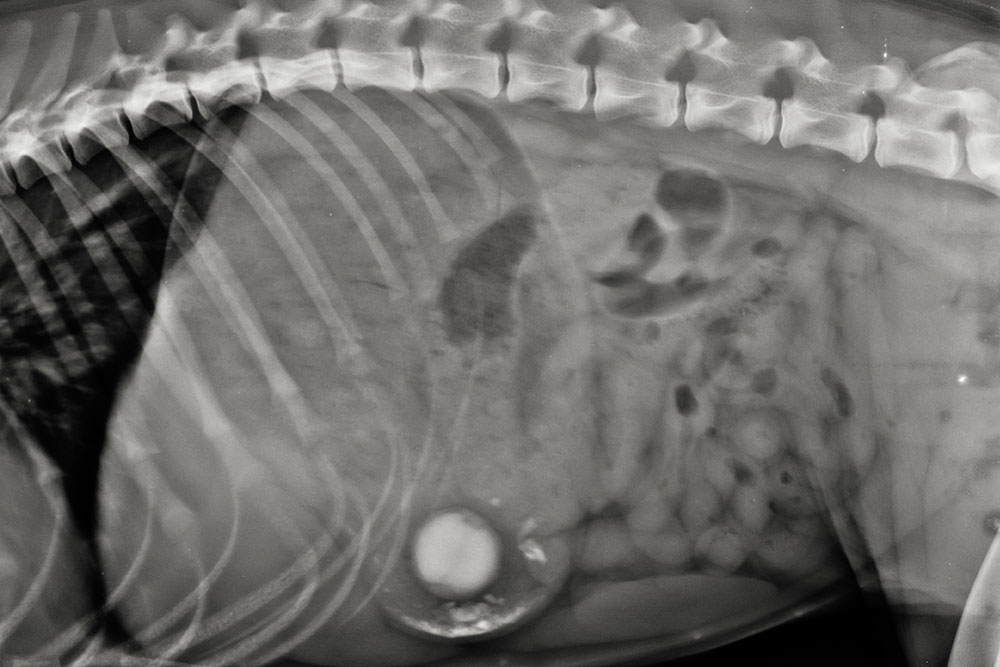

X-rays and Ultrasound

X-rays are often the first tool used, especially for locating metallic or dense objects. For softer materials, ultrasound may provide better visibility. More on gastrointestinal foreign bodies here.